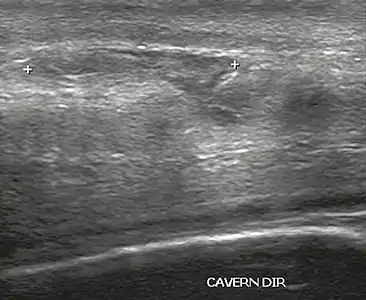

خِلال الفَحص بالموجات فَوْق الصَّوْتِيَّة، تَظهر آفَةُ الغلالة البَيْضاء على أَنها انْقِطاع في (فقدان استمرارية) خَط الصَّدى الَّذِي يُمَثلها (الشكل 4). التورمات الدَّمَوِيَّة صَغيرة، مُتَوَسطَة، أو واسعة تُحَدد مَدَى هذا الِانْقِطَاع. يُمكِن مُلاحظة التورمات الدَّمَوِيَّة داخل الكَهف، في بَعْضِ الأَحيان بِدُون وُجود كسر في الغلالة البَيضاء، عِندَما يَكون هُنَاكَ آفة في العضلاتِ المَلساء في الترابيق المُحِيطَة بالمساحات الجيبية.[9]

الشَّكْل 4 أ: الْمَوْجَات فَوْق الصَّوْتِيَّة للقضيب، المسقط الجانبي الأَيْمَن. مَقْطَع طُولِي يُظهر تَمَزُّق الغلالة البَيضاء مع وَرَم دَمَوِيّ مُجاور يَبْلُغ 1.92 سم، بِسَبَب الرَضْح.[9]